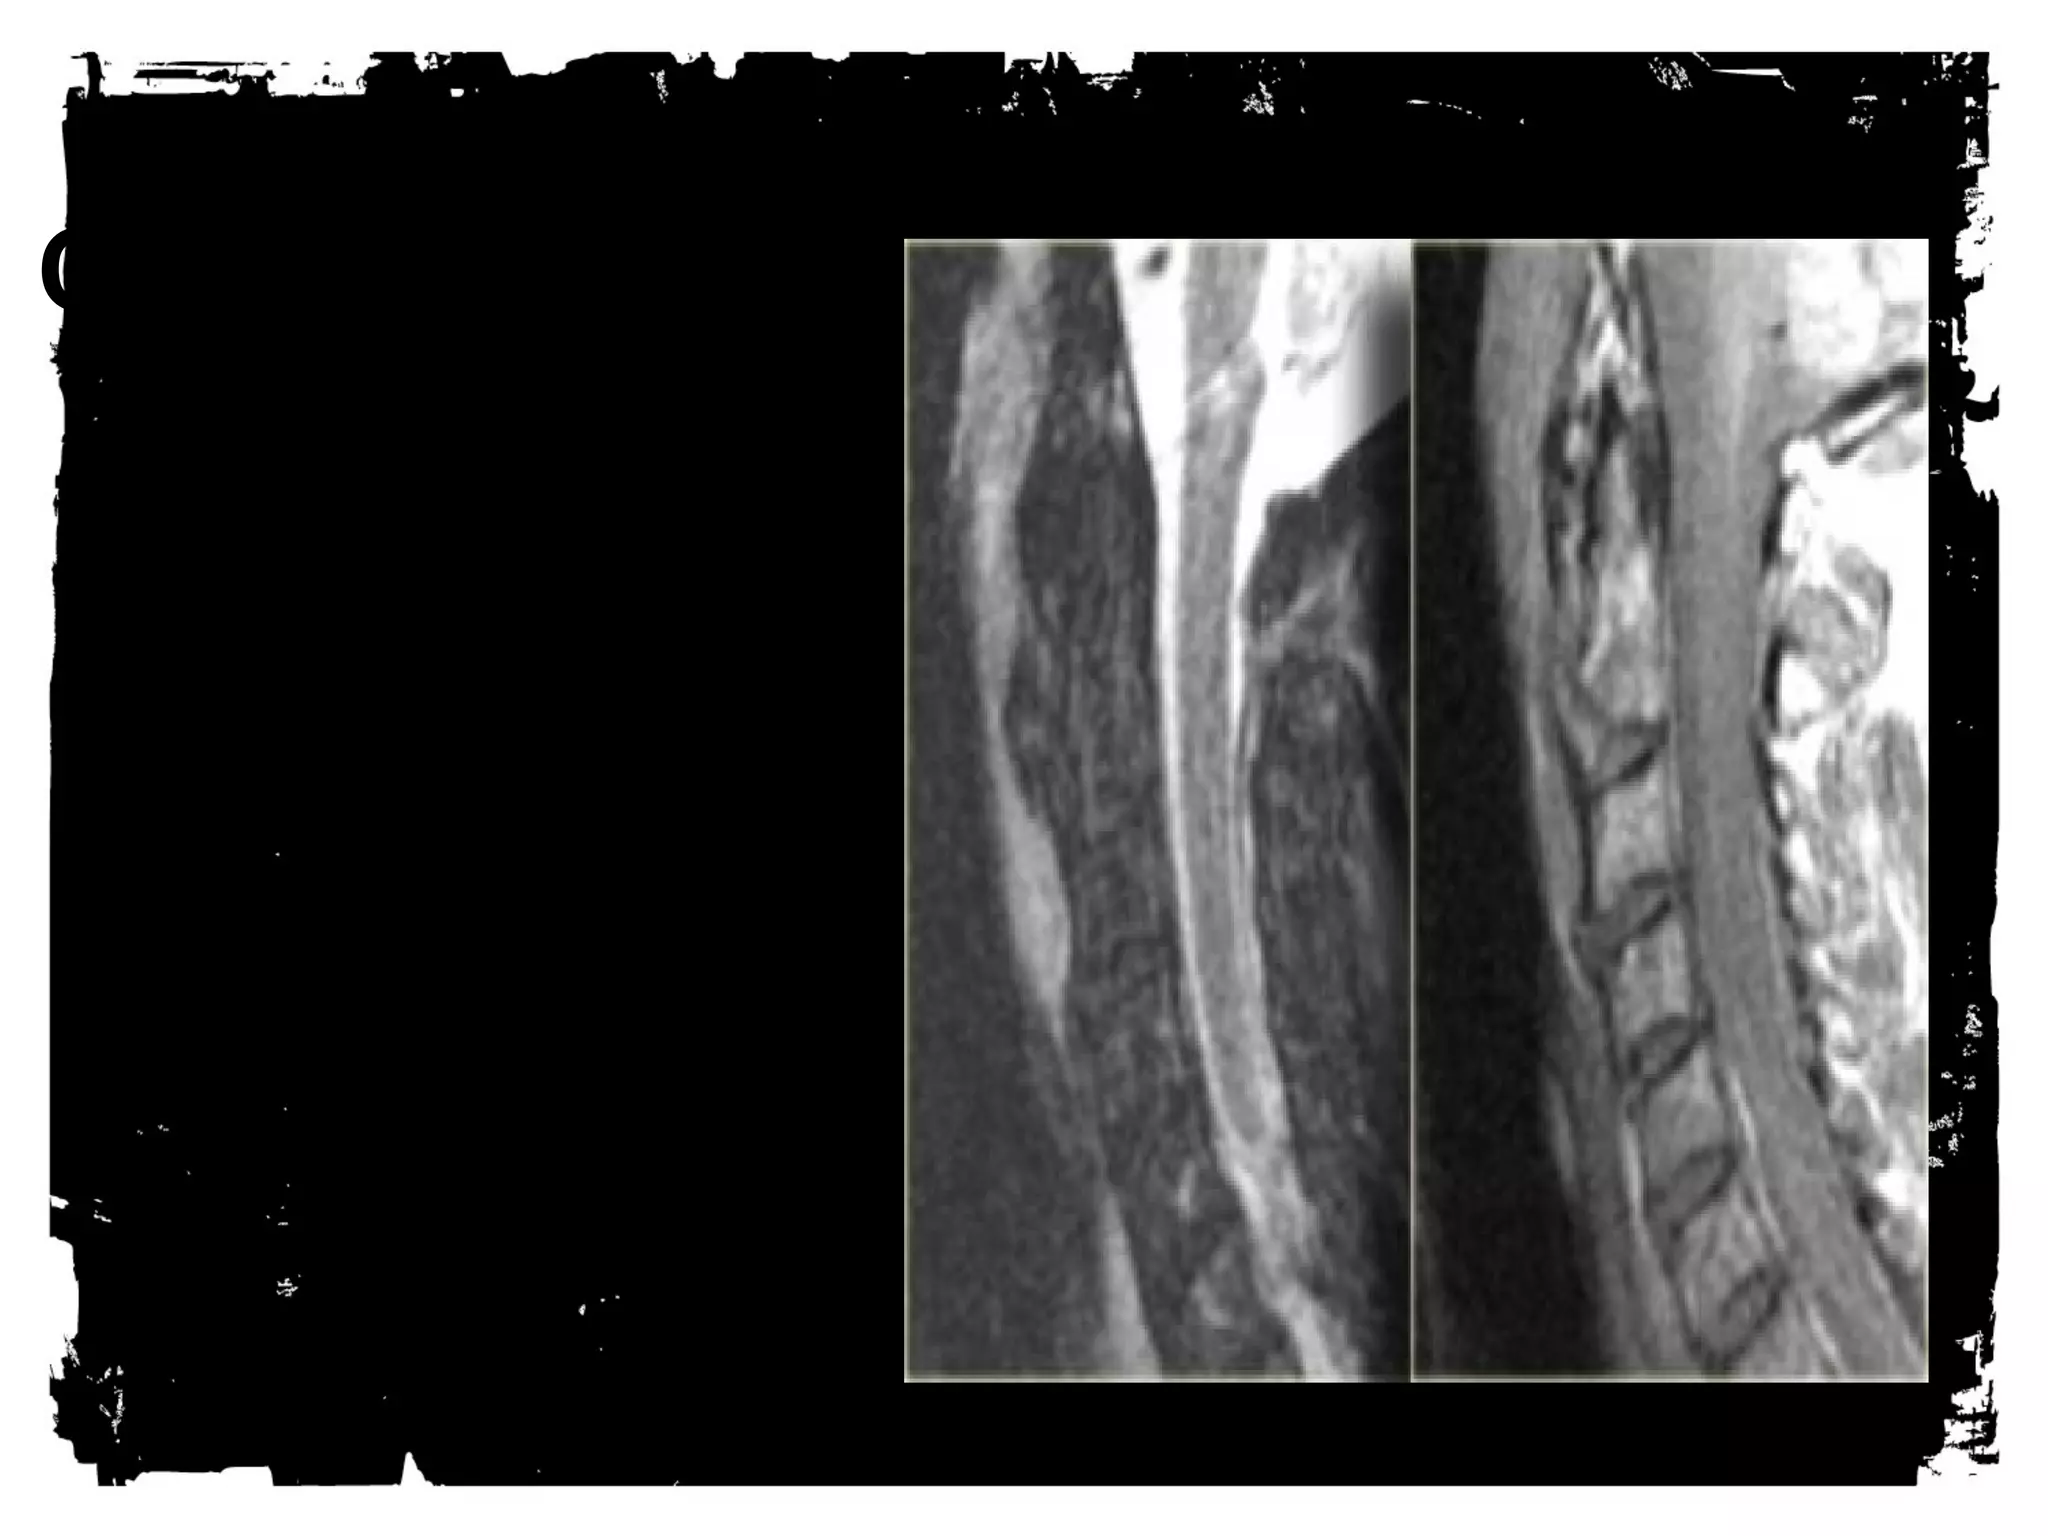

Spinal cord injury (SCI)

Spinal cord injury

There are two types of

injury to the spinal cord:

• Non-hemorrhagic with

only high signal on MR

due to edema.

• Hemorrhagic with areas of

low signal intensity within

the area of edema.

• There is a strong correlation

between the length of the

spinal cord edema and the

clinical outcome.

• The most important factor

however is whether there is

hemorrhage, since

hemorrhagic spinal cord

injury has an extremely poor

outcome.

Midsagittal (a) T1-weighted and (b) T2-weighted MR images obtained in 45-

year-old man with acute traumatic C5 through C6 mild SCI after a fall show

the distances of the spinal canal and spinal cord at the injury site (Di and di,

respectively), one segment below the injury site (Db and db, respectively), and

one segment above the injury site (Da and da, respectively) used to (a)

estimate the MCC and (b) measure spinal canal compression.

©2007 by Radiological Society of North America